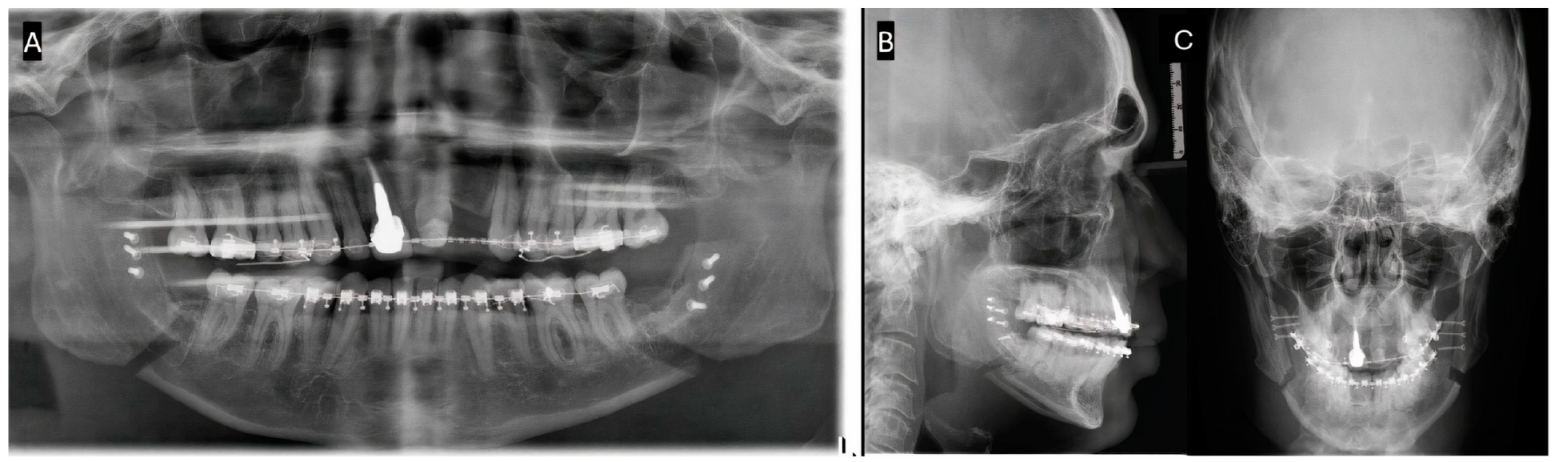

2. Case Report